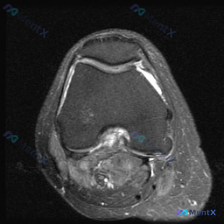

这是一例膝关节轴位T2加权MRI图像,涵盖股骨髁间窝、髌股关节及周围软组织,具体影像发现如下:

- 骨骼结构:股骨远端骨皮质及骨松质信号未见明显异常

- 关节软骨:髌骨关节面软骨不均匀高信号、边缘轮廓模糊;股骨滑车关节软骨信号增高、不连续,提示软骨异常

- 关节腔:髌股关节间隙及侧隐窝可见明显条带状高信号,存在关节积液

- 交叉韧带:髁间窝交叉韧带断面周围可见明显异常信号,结构边界欠清晰,提示水肿或炎性改变

- 周围软组织:髌下脂肪垫及周围滑膜区域信号混杂高信号,提示滑膜炎或脂肪垫炎症;关节周围前后侧软组织弥漫水肿高信号,存在炎性渗出或创伤性反应